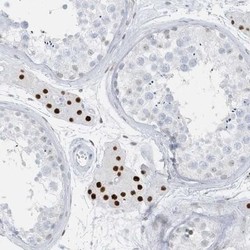

- Main image

- Experimental details

- Immunohistochemistry-Paraffin: AP000322.53 Antibody [NBP1-91141] - Staining of human testis shows strong nuclear positivity in cells in seminiferus ducts.